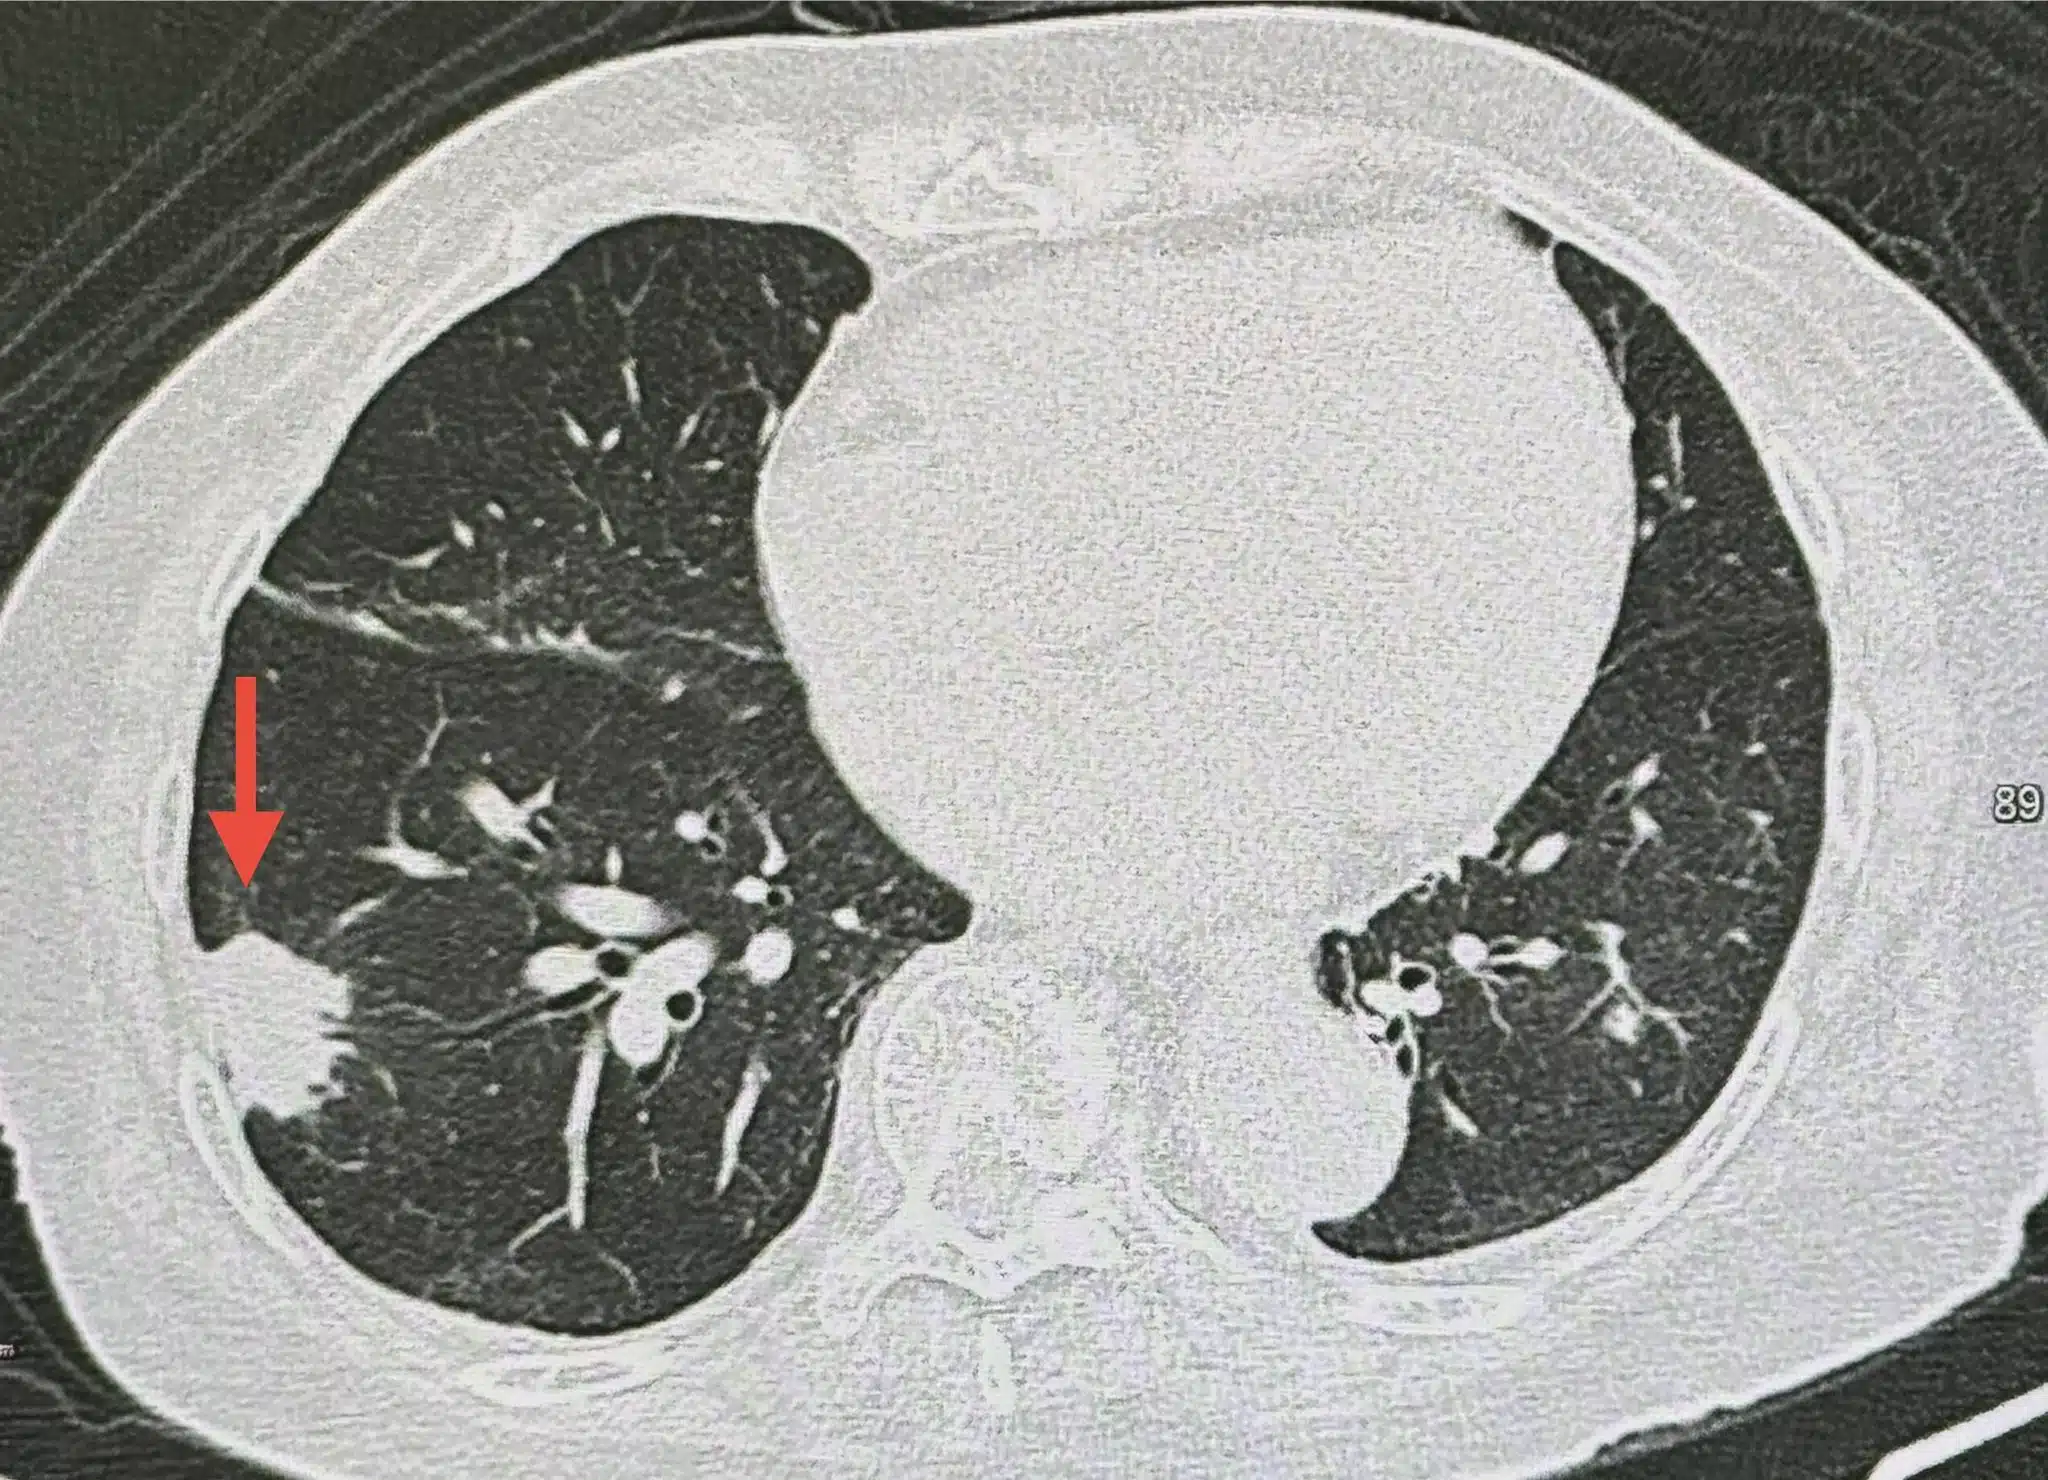

แต่ผลการตรวจทางแพทย์กลับพบความผิดปกติ ซึ่งภาพเอกซเรย์ปอด พบเงาผิดปกติที่ปอดข้างขวาด้านบน (รอยโรคเดิมจากวัณโรค) แต่สิ่งที่น่ากังวลคือ พบก้อนเนื้อใหม่ขนาด 1.9 x 1.9 เซนติเมตร ที่ปอดข้างขวาด้านล่าง ปีก่อนหน้านี้ไม่เคยมี จากเอกซเรย์คอมพิวเตอร์ (CT Scan) พบก้อนขนาดใหญ่ขึ้นเป็น 3.0 × 2.4 × 2.0 เซนติเมตรที่ปอดขวาด้านล่าง ส่วนผลเลือดค่าบ่งชี้มะเร็งทุกตัวปกติ

จากนั้นแพทย์จึงตัดสินใจใช้เข็มเจาะก้อนเนื้อดังกล่าวเพื่อส่งตรวจทางพยาธิวิทยา ผลปรากฏว่าไม่ใช่เนื้องอกร้าย แต่เป็นภาวะปอดอักเสบจากการติดเชื้อรา ‘คริปโตค็อกคัส’ (Cryptococcus)